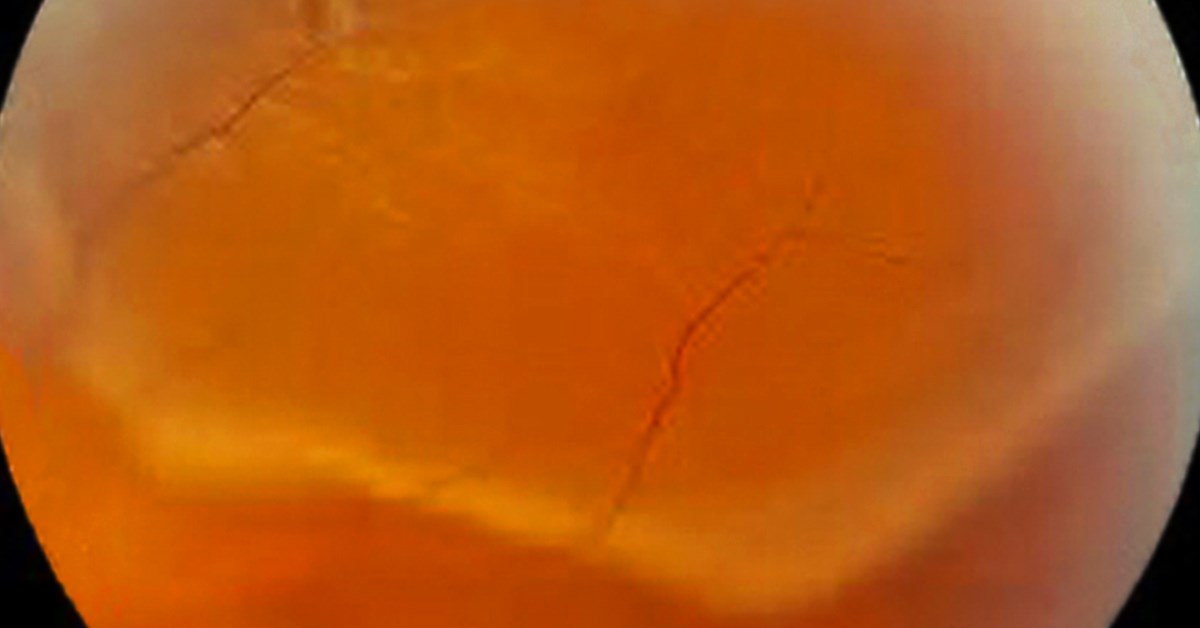

Have you been seeing “stars?” As we get older, the vitreous, or clear gel that fills our middle eye, can shrink and pull away from the Retina. When this happens you may notice what look like “stars” or flashing lights, which could be a sign of a Detached Retina, a serious sight threatening eye condition. If you ever experience seeing what look like “stars,” please call High Country Macula immediately to rule out possible causes including a Detached Retina, a Retinal Tear, or symptom of another emergency.